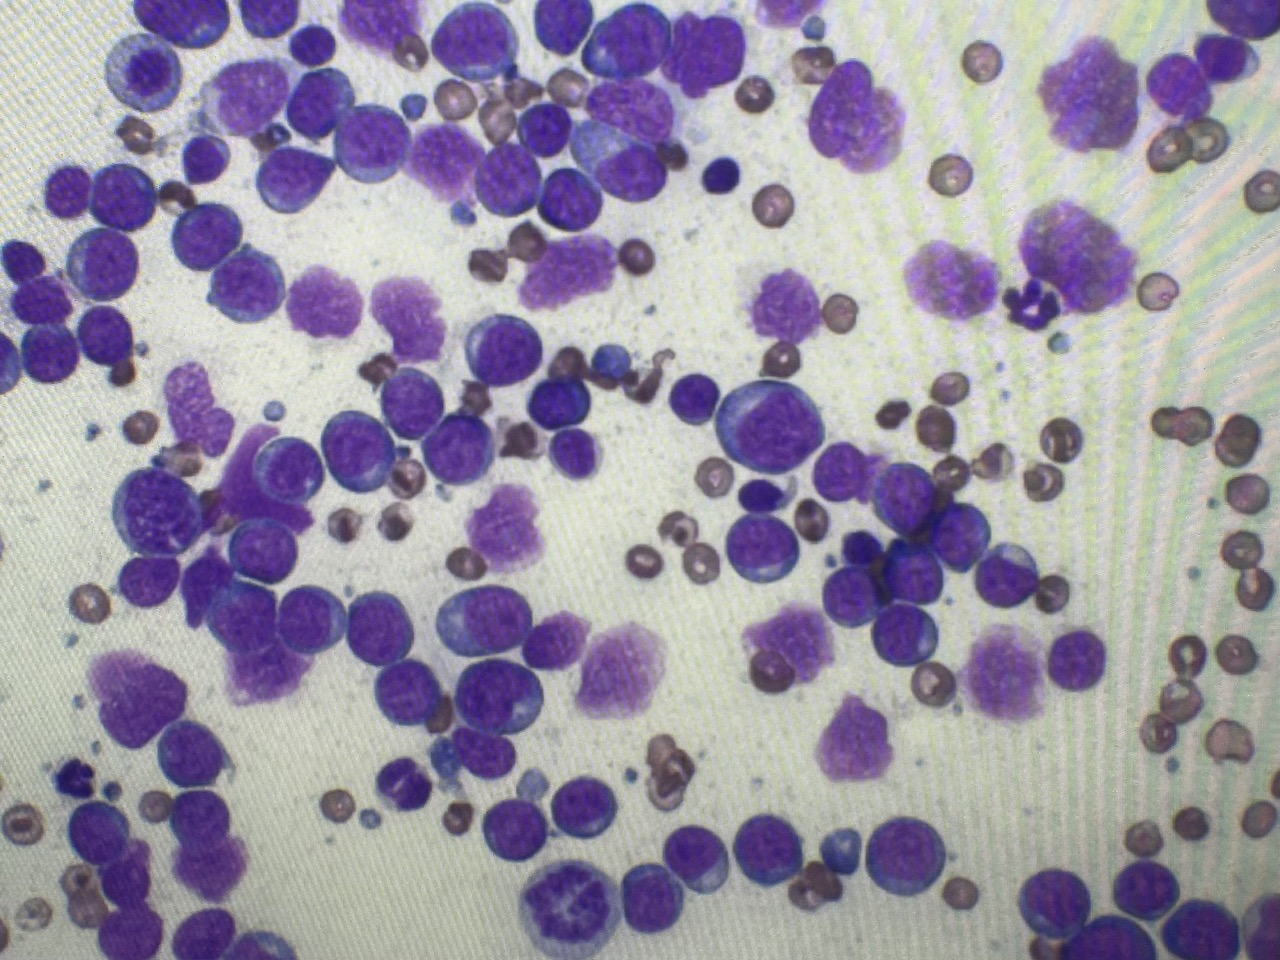

今回は「犬の多中心型リンパ腫」について解説しております。犬の悪性がんのひとつで早期発見・早期治療が望まれる病気です。ぜひご参考にされてください。